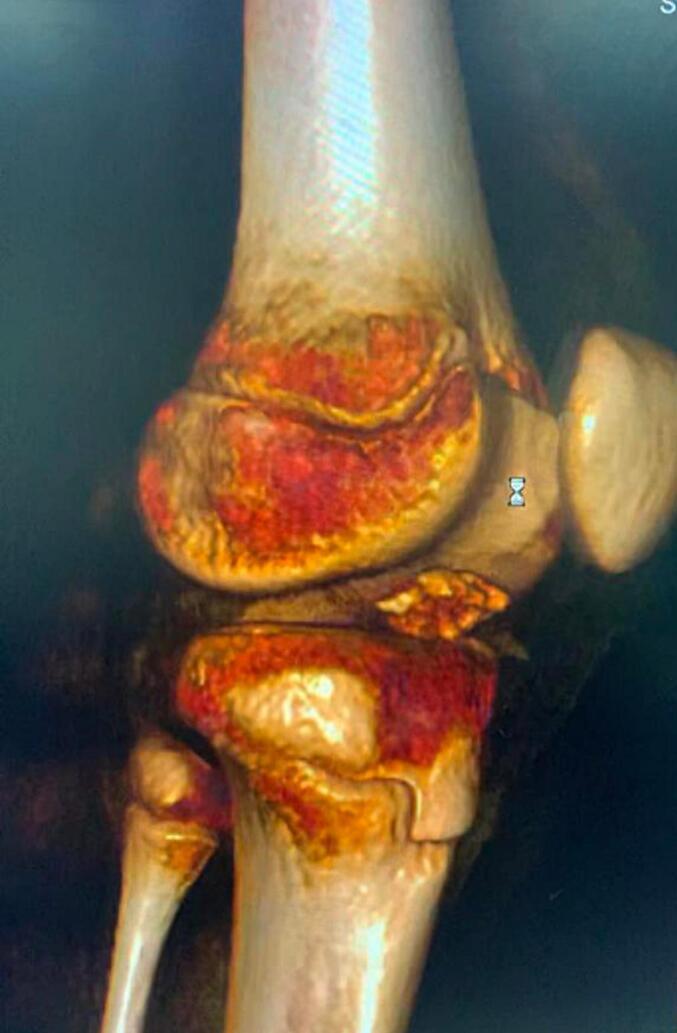

Distal anterior cruciate ligament avulsion from tibial side is an unusual injury. It can be either bony avulsion, which is more common, or rarely a soft tissue peeling of tibial spine with no bone injury. This case report represents a very infrequent injury of combined soft tissue peeling of distal anterior cruciate ligament along with bony avulsion of tibial spine in a 12-years-old boy after falling from his bike.

前交叉韧带从胫骨侧远端撕脱是一种不常见的损伤。它可以是较为常见的骨性撕脱,或者极少情况下是胫骨棘的软组织剥离且无骨质损伤。本病例报告呈现了一名12岁男孩从自行车上摔下后,前交叉韧带远端合并软组织剥离及胫骨棘骨性撕脱这种非常罕见的损伤情况。